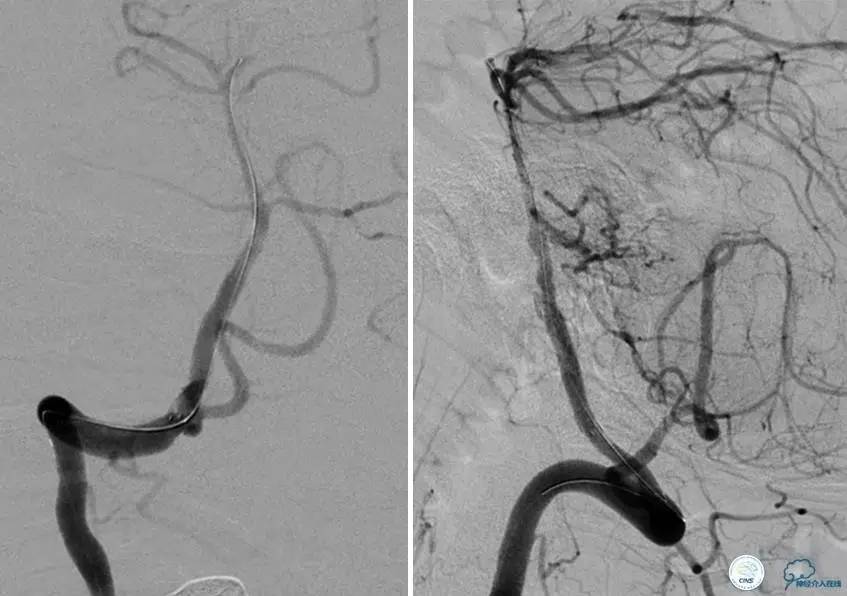

▼DSA示右侧椎动脉发育低下,弥漫性狭窄,可以看到左侧椎动脉反流,因此判断左侧椎动脉V4段CTO。

治疗:

微导丝穿过闭塞段,微导管造影,球扩闭塞段,置入Wingspan支架,血流完全恢复正常。